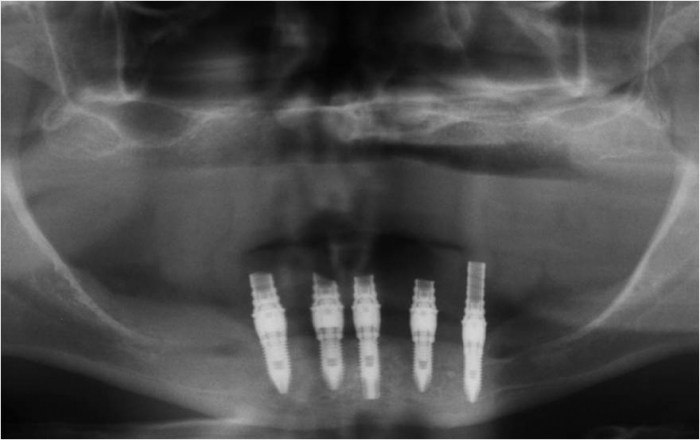

Raio X inicial

Imagens dos implantes inferiores e prótese fixa provisória imediata